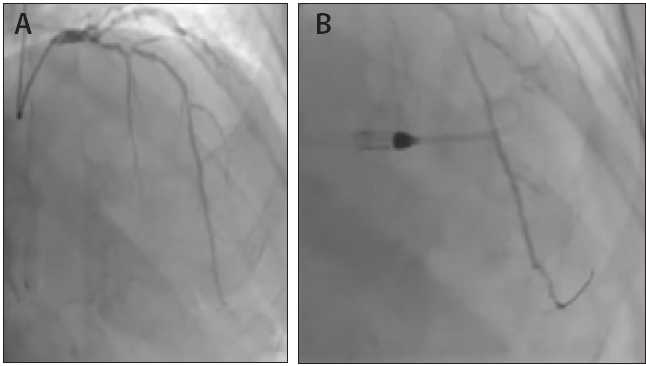

Figure 1. Diagnostic angiogram showing the extent of disease (A). Anteroposterior cranial projection depicting long segment of heavily calcified subtotally occluded mid LAD (B).

Coronary angiography showed extensive calcification in the coronary arteries. The angiogram also showed a large but heavily diseased and calcified left anterior descending (LAD) artery subtotaled in the mid-segment (Figures 1A and 1B). The disease extended into the distal left main coronary artery, and high-grade disease was present in the proximal obtuse marginal branch and also included a medium but dominant right coronary artery with a 70% to 80% lesion distally.